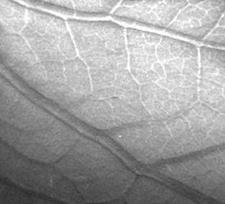

Рис. 2. Изображение древесного листа,

полученное методом рефракционной интроскопии.

где a - угол между пучком и преломляющей поверхностью, n - показатель преломления, l - длина волны, выраженная в ангстремах. Величина рефракционного контраста определяется относительным локальным изменением интенсивности пучка, испытавшего отклонение на угол a. Для цилиндрического объекта наибольший контраст возникает на его краях, поэтому изображения кажутся объемными (см., например, рис.2). Подробный расчет контраста и дозы облучения для рефракционной интроскопии можно найти в [4].